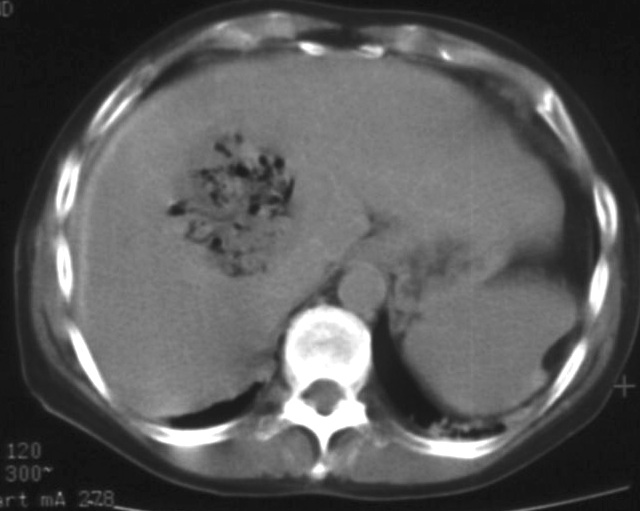

TAE (Transcatheter Arterial Embolization) and TACE (Transcatheter Arterial ChemoEmbolization) are methods with which the supplying artery/arteries of the tumor are selectively approached through the branches of the hepatic artery. When the catheter is in position the tumor branches are injected with a special, oily contrast material, Lipiodol (TAE). The injected material is used as an embolization material (figure 18.), other chemotherapeutical drugs (5-Fluoro-Uracil, Epirubicin, Cisplatin, Mytomicin-C) can also be used (TACE) (figure 19.).

Image

Figure 19. – TACE, CT control (2 weeks after treatment)